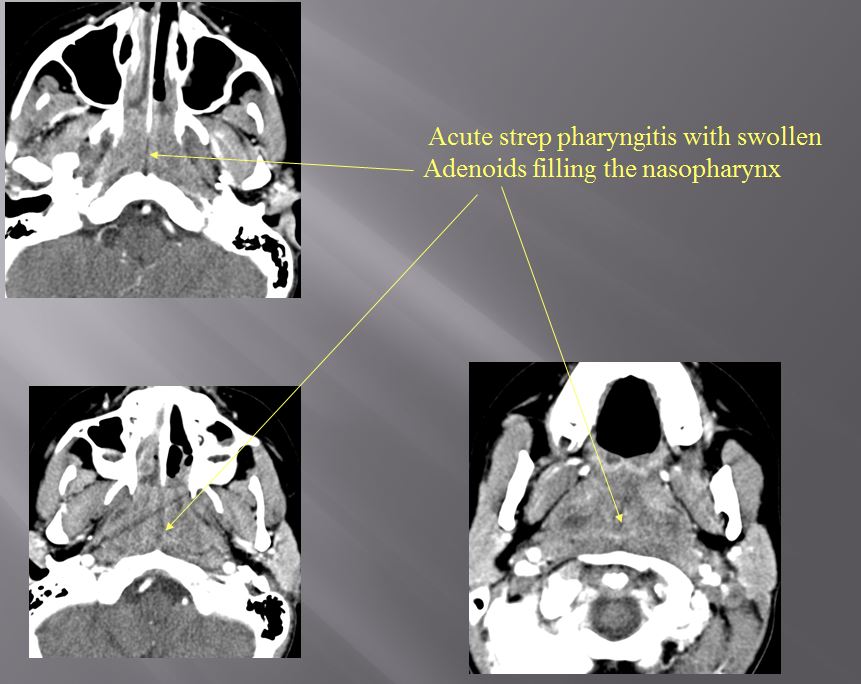

Nasopharynx

There is excessive enhancement or thickening of the mucosa or hypertrophy of the lymphoid tissue in the nasopharynx. [Yes/No]

There is evidence of an abscess within the lymphoid tissue of the nasopharynx. [Yes/No]